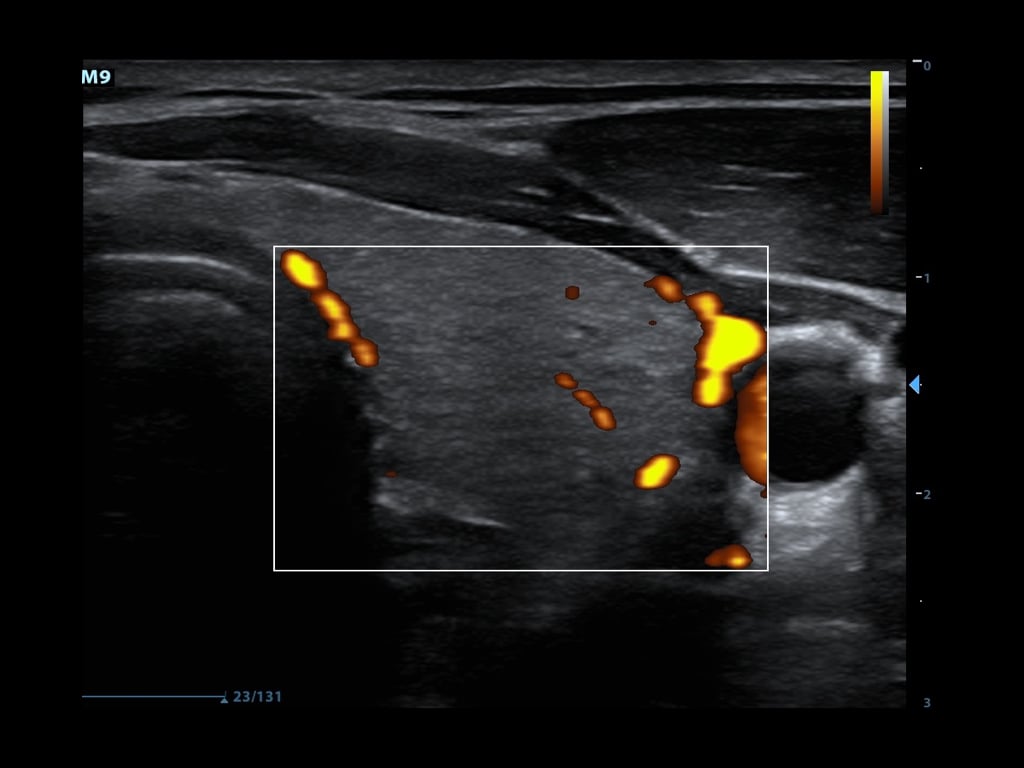

- Power Doppler looks only at the amplitudes of the returning frequency shifts.

- It does not examine flow velocity or the direction of flow

- This allows for detection of movement in very low flow states (Figure 4)

- This is of use when examining vascular emergencies such as testicular or ovarian torsion

- Figure 4. Power doppler showing blood flow in thyroid tissue